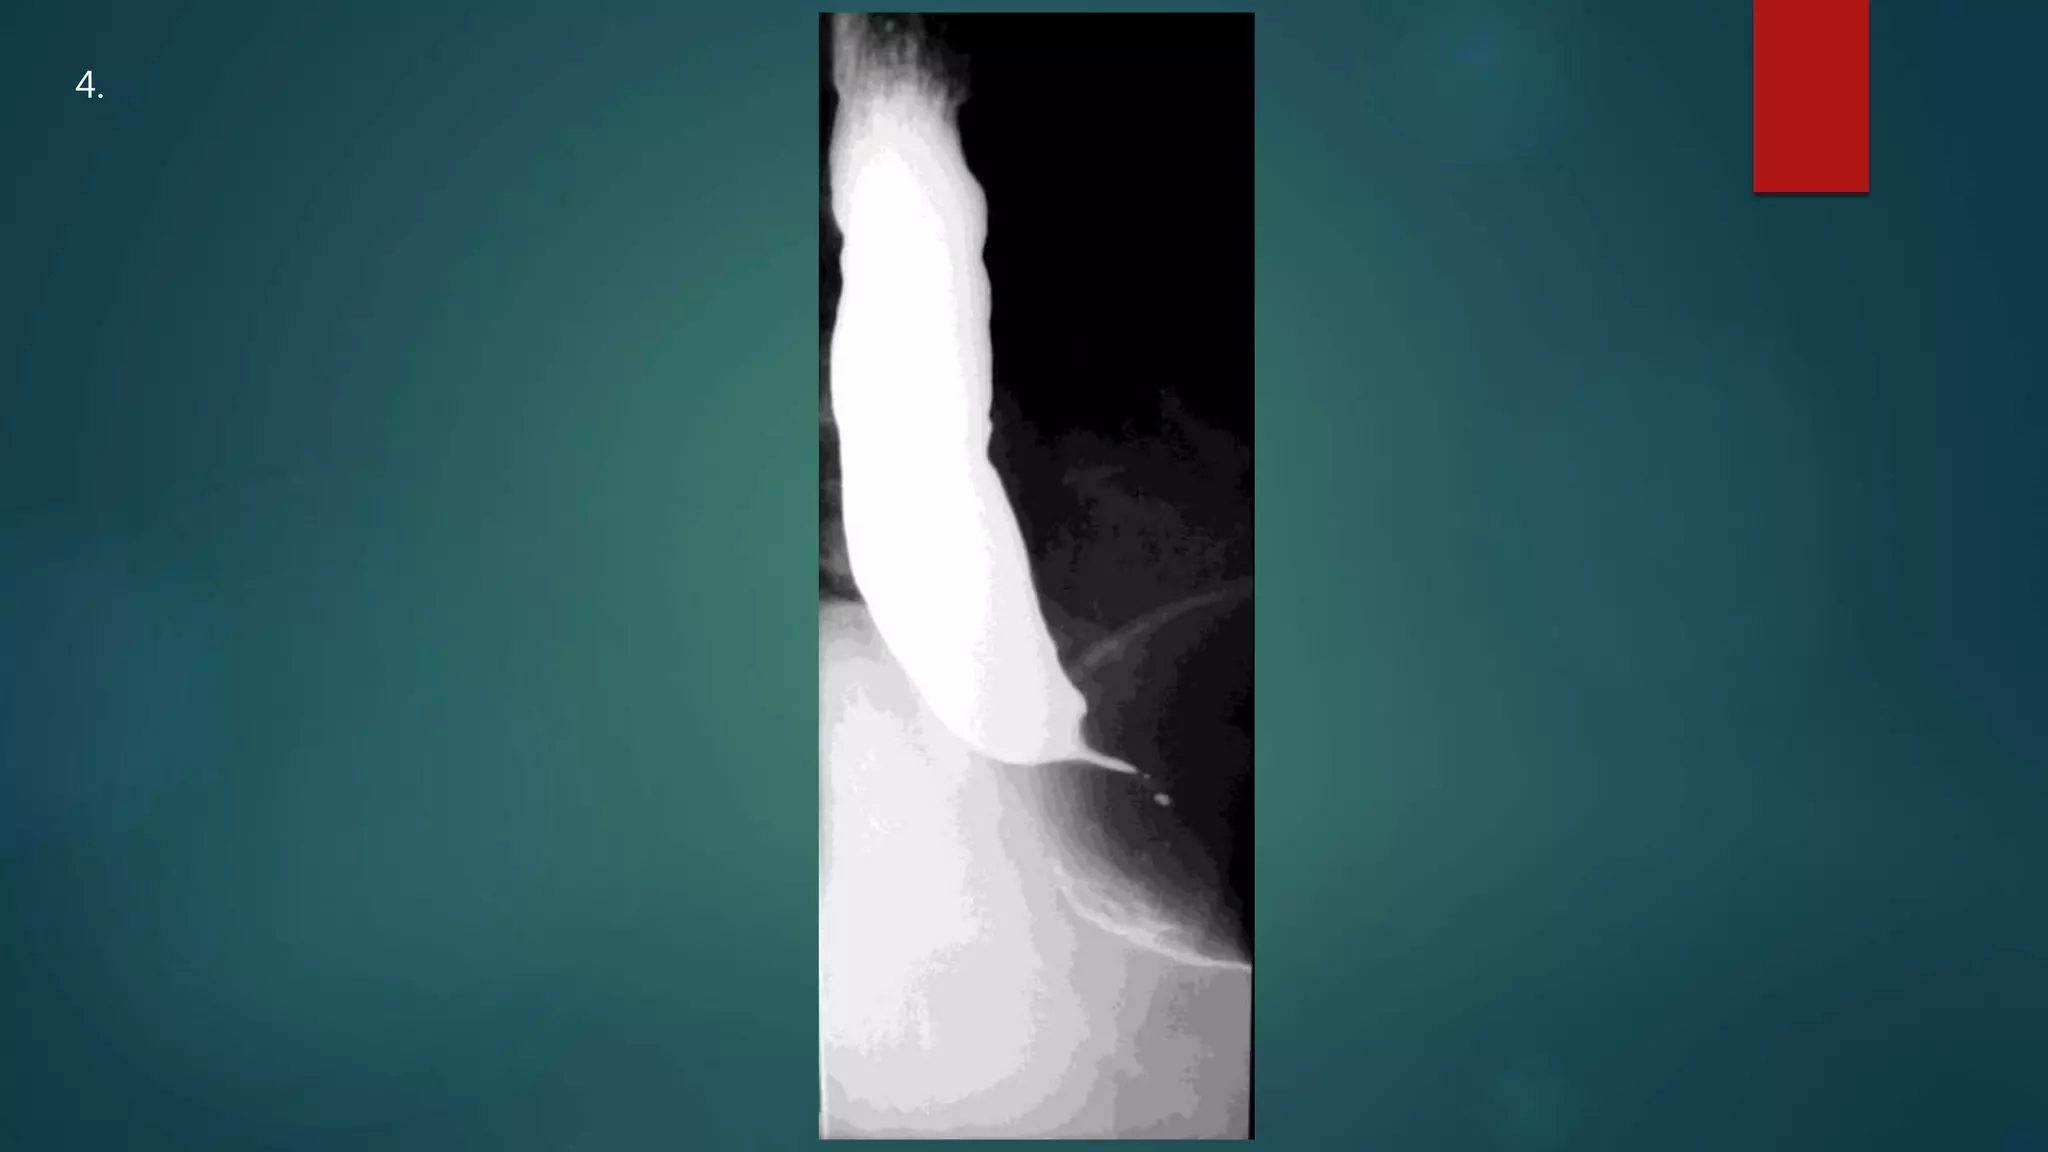

This document appears to be a medical report discussing several patients. It mentions a 35-year-old who was in a severe motor vehicle accident and an 81-year-old with a history of a non-vegetarian diet who had a perforated bowel from a chicken bone. The document provides few other details across its 25 numbered entries and was authored by Dr. Anish Choudhary for junior year 3 on May 30, 2016.